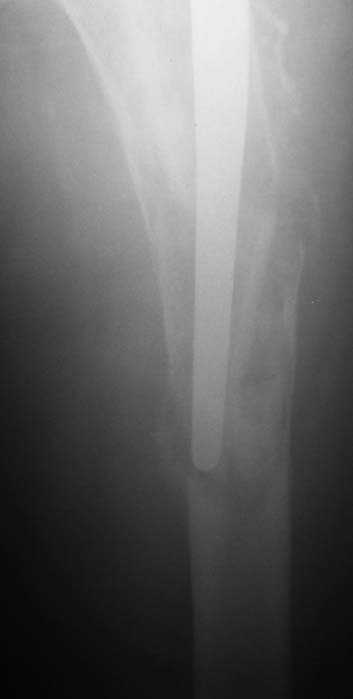

Мужчина, 39 лет.По поводу двустороннего асептического некроза головок бедренных костей последовательно выполнено тотальное эндопроезирование левого (1998 г), затем правого (1999 г) тазобедренных суставов.

26/06/06

С 2001 г отмечает нарастающие боли в левом бедре. Предполагается удаление протеза, удаление цемена из канала бедра, пластика дефекта бедренной кости.

Нет никакого смысла делать операцию в два этапа. С чашкой все понятно - стандартный подход с установкой пресс-фит компонента. На бедре имеет

место перипротезный перелом В3 типа - т.е. перелом вокруг ножки с ее нестабильностью на фоне выраженного остеолиза. Решение - доступ к каналу

через перелом с удалением самой ножки, костного цемента и рубцовых тканей. Установка ножки дистальной фиксации (типа Solution), длину ножки

надо определить по шаблону. Минимальный контакт ножки с интактной костью - 6-8 см. Фрагменты проксмального отдела собираются на ножке

эндопротеза, дефекты костной ткани заполняются чипсами (аллографт) и фиксируются кортикальными аллографтами, уложенными дополнительно по типу

"вязанки хвороста" серкляжом. Мы имеем 8 или 10 подобных наблюдений и результатами довольны.

Абсолютно согласен.Это проверенный путь.Единственное, под Solution надо тщательно удалить цемент из бедра куда встанет дистальная часть ножки.Иначе при установке расколите диафиз бедра.Было поначалу такое у нас.С уважением